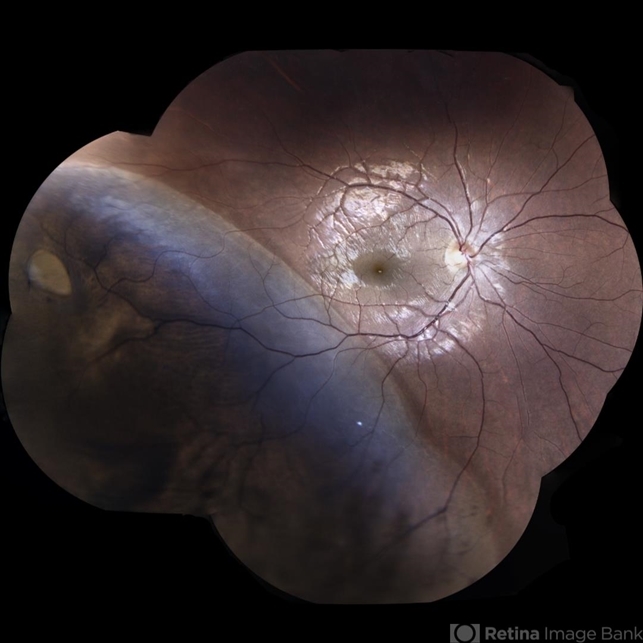

- retinal detachment with retinal defect

- Eidon AF

- Fundus mosaic of an 26-year-old woman with macula ON retinal detachment with 9 o'clock retina tear.